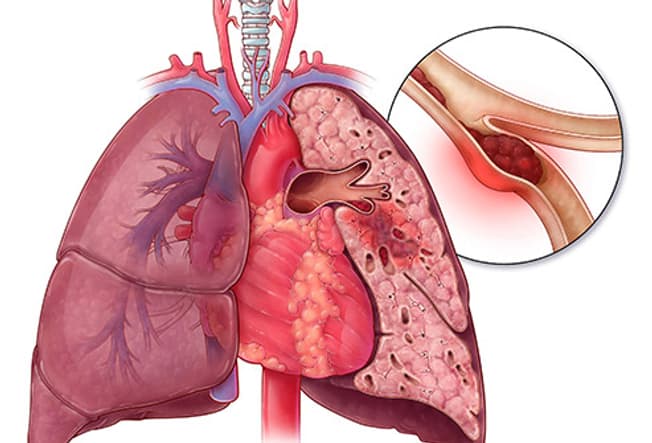

Pulmonary Embolism (PE)

A blood clot in your legs can break off and travel all the way up to your lungs. When that happens, it’s called a pulmonary embolism. The clot can block the flow of blood in your lungs. Without blood, they can’t work as well as they should. They won’t be able to release enough oxygen to supply the rest of your body. PE can cause chest pain and shortness of breath. It could be life-threatening if you don’t get treated right away.